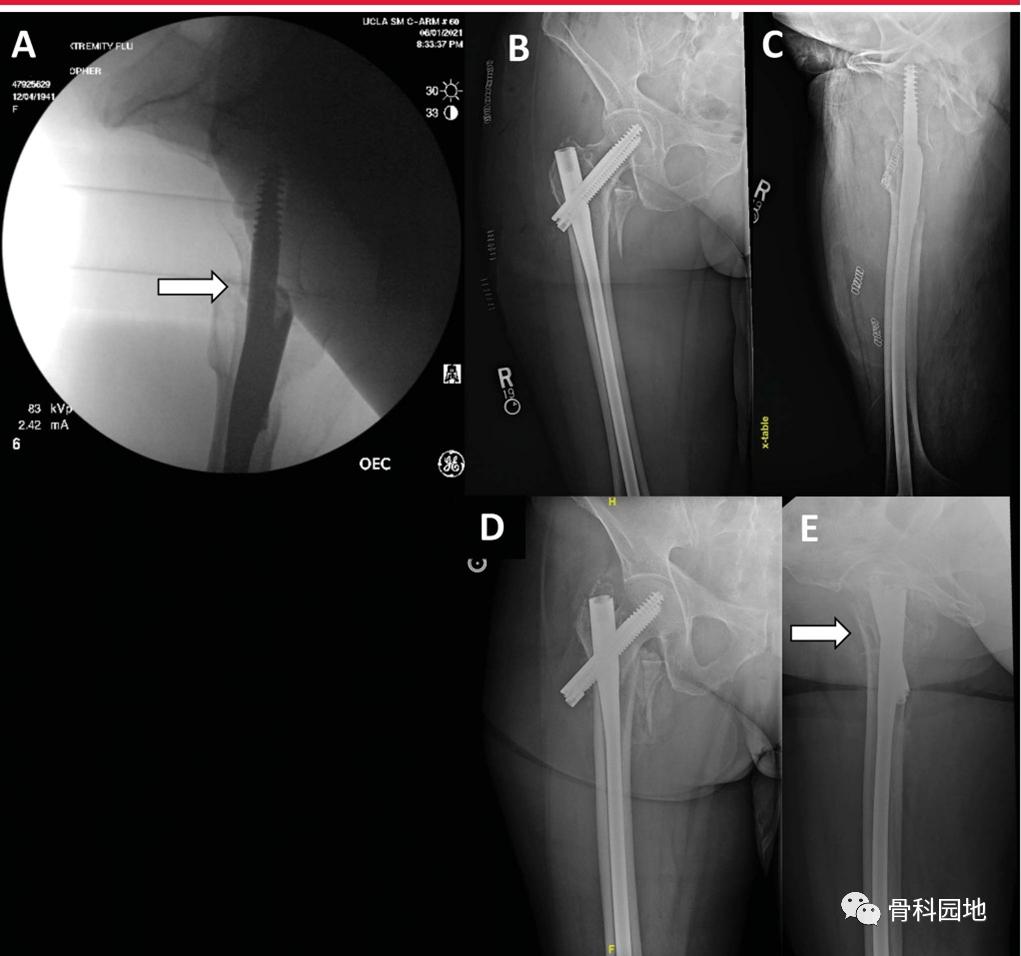

影像学复位的关键评估需要评估前内侧皮质支撑。由于股骨距在转子周围骨折中经常被破坏和粉碎,前内侧皮质支撑为骨折碎片的伸缩提供了最终的结构约束。在AP视图上,解剖性或阳性的前内侧皮质支撑可减少骨折的可控塌陷。

A,侧位复位图显示皮质前内侧支撑(箭头)。B,术后AP图像显示皮质对齐。C,术后侧位图像显示前内侧皮质支撑变形。D-E, AP和侧位图显示术后6周明显塌陷(箭头)。

外侧的解剖复位可能很难,这可能是因为髂股韧带强大的限制。可以防止股骨颈前移位。可使用的技术是沿内侧和下颈部由前向后放置Schanz针。这可以使前内侧皮质支撑提升到解剖复位和/或正复位。